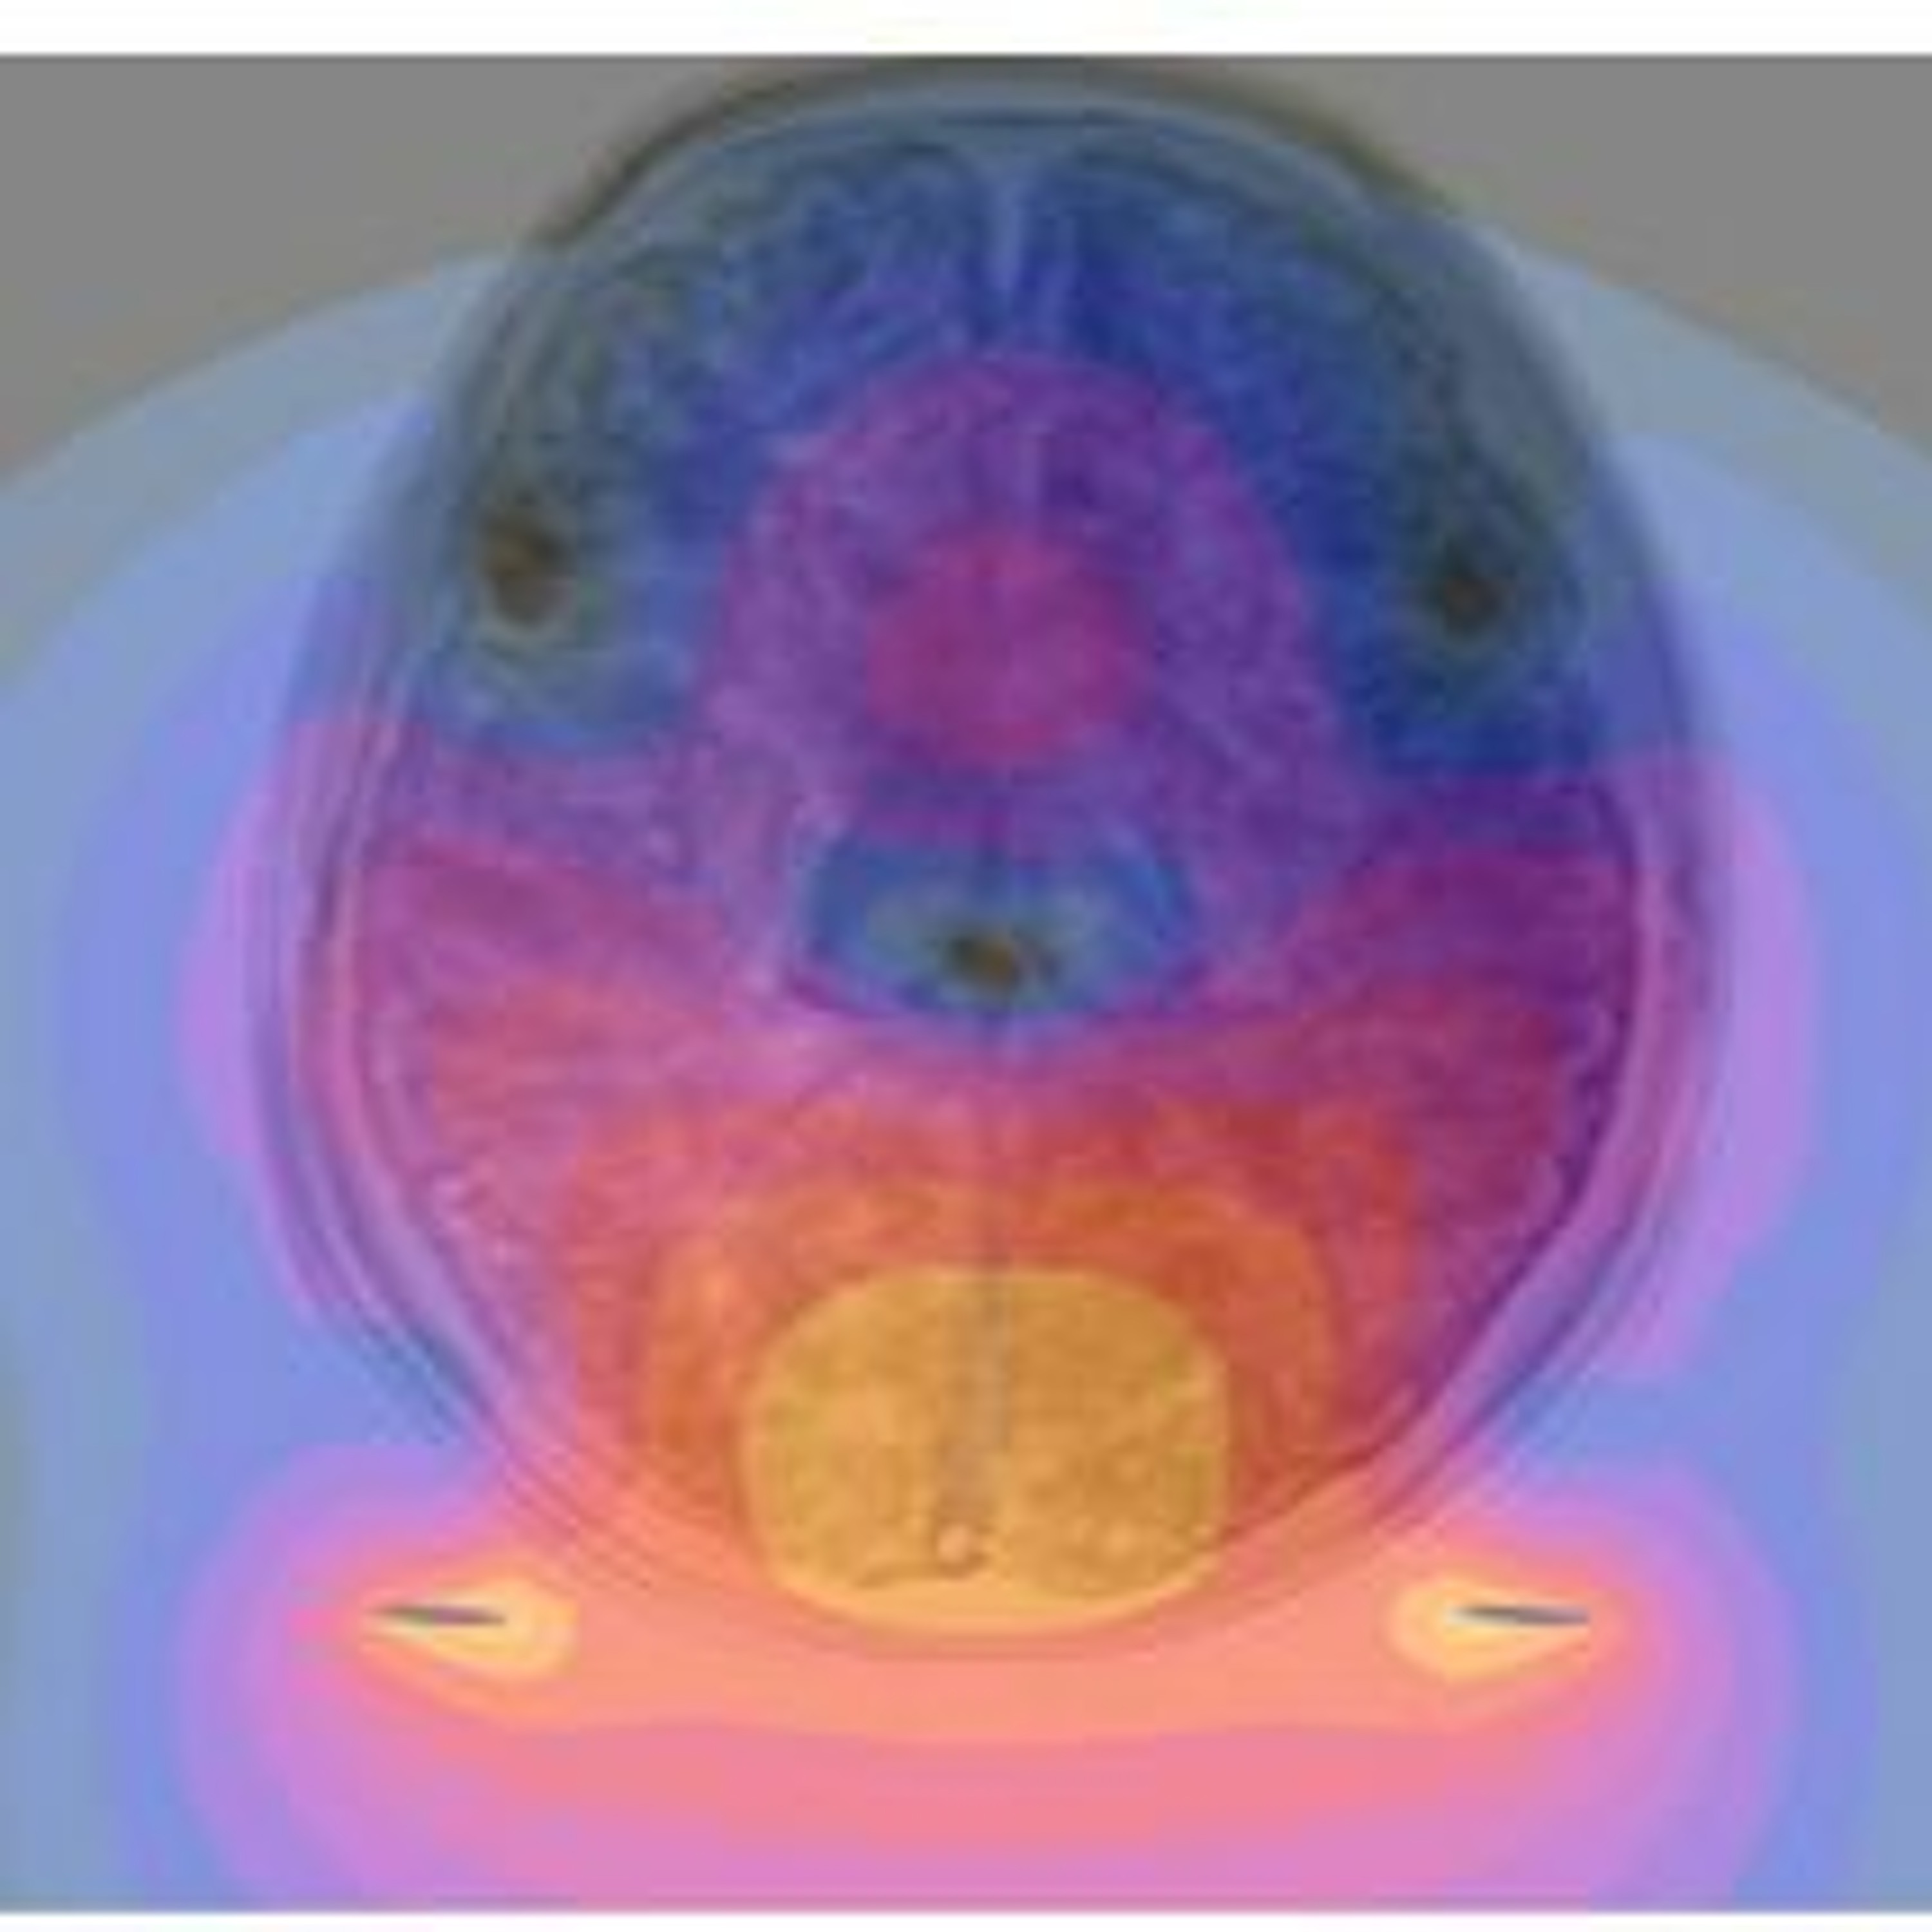

Advanced image-capturing technology for MRI scanners paired with powerful computers, allow researchers to quickly detect and analyze the smallest changes in brain function after a concussion. Radiologist Pratik Mukherjee of the University of California, San Francisco explains how it works.

“With the latest technology that we are starting to apply, we can actually get several images of the brain within one second. So we can image the entire brain in less than a second. And we do it continually during the scan for many minutes so we are getting thousands, even tens of thousands images of the brain, which are snapshots over time of function in the brain and the way different brain regions connected to each other.”